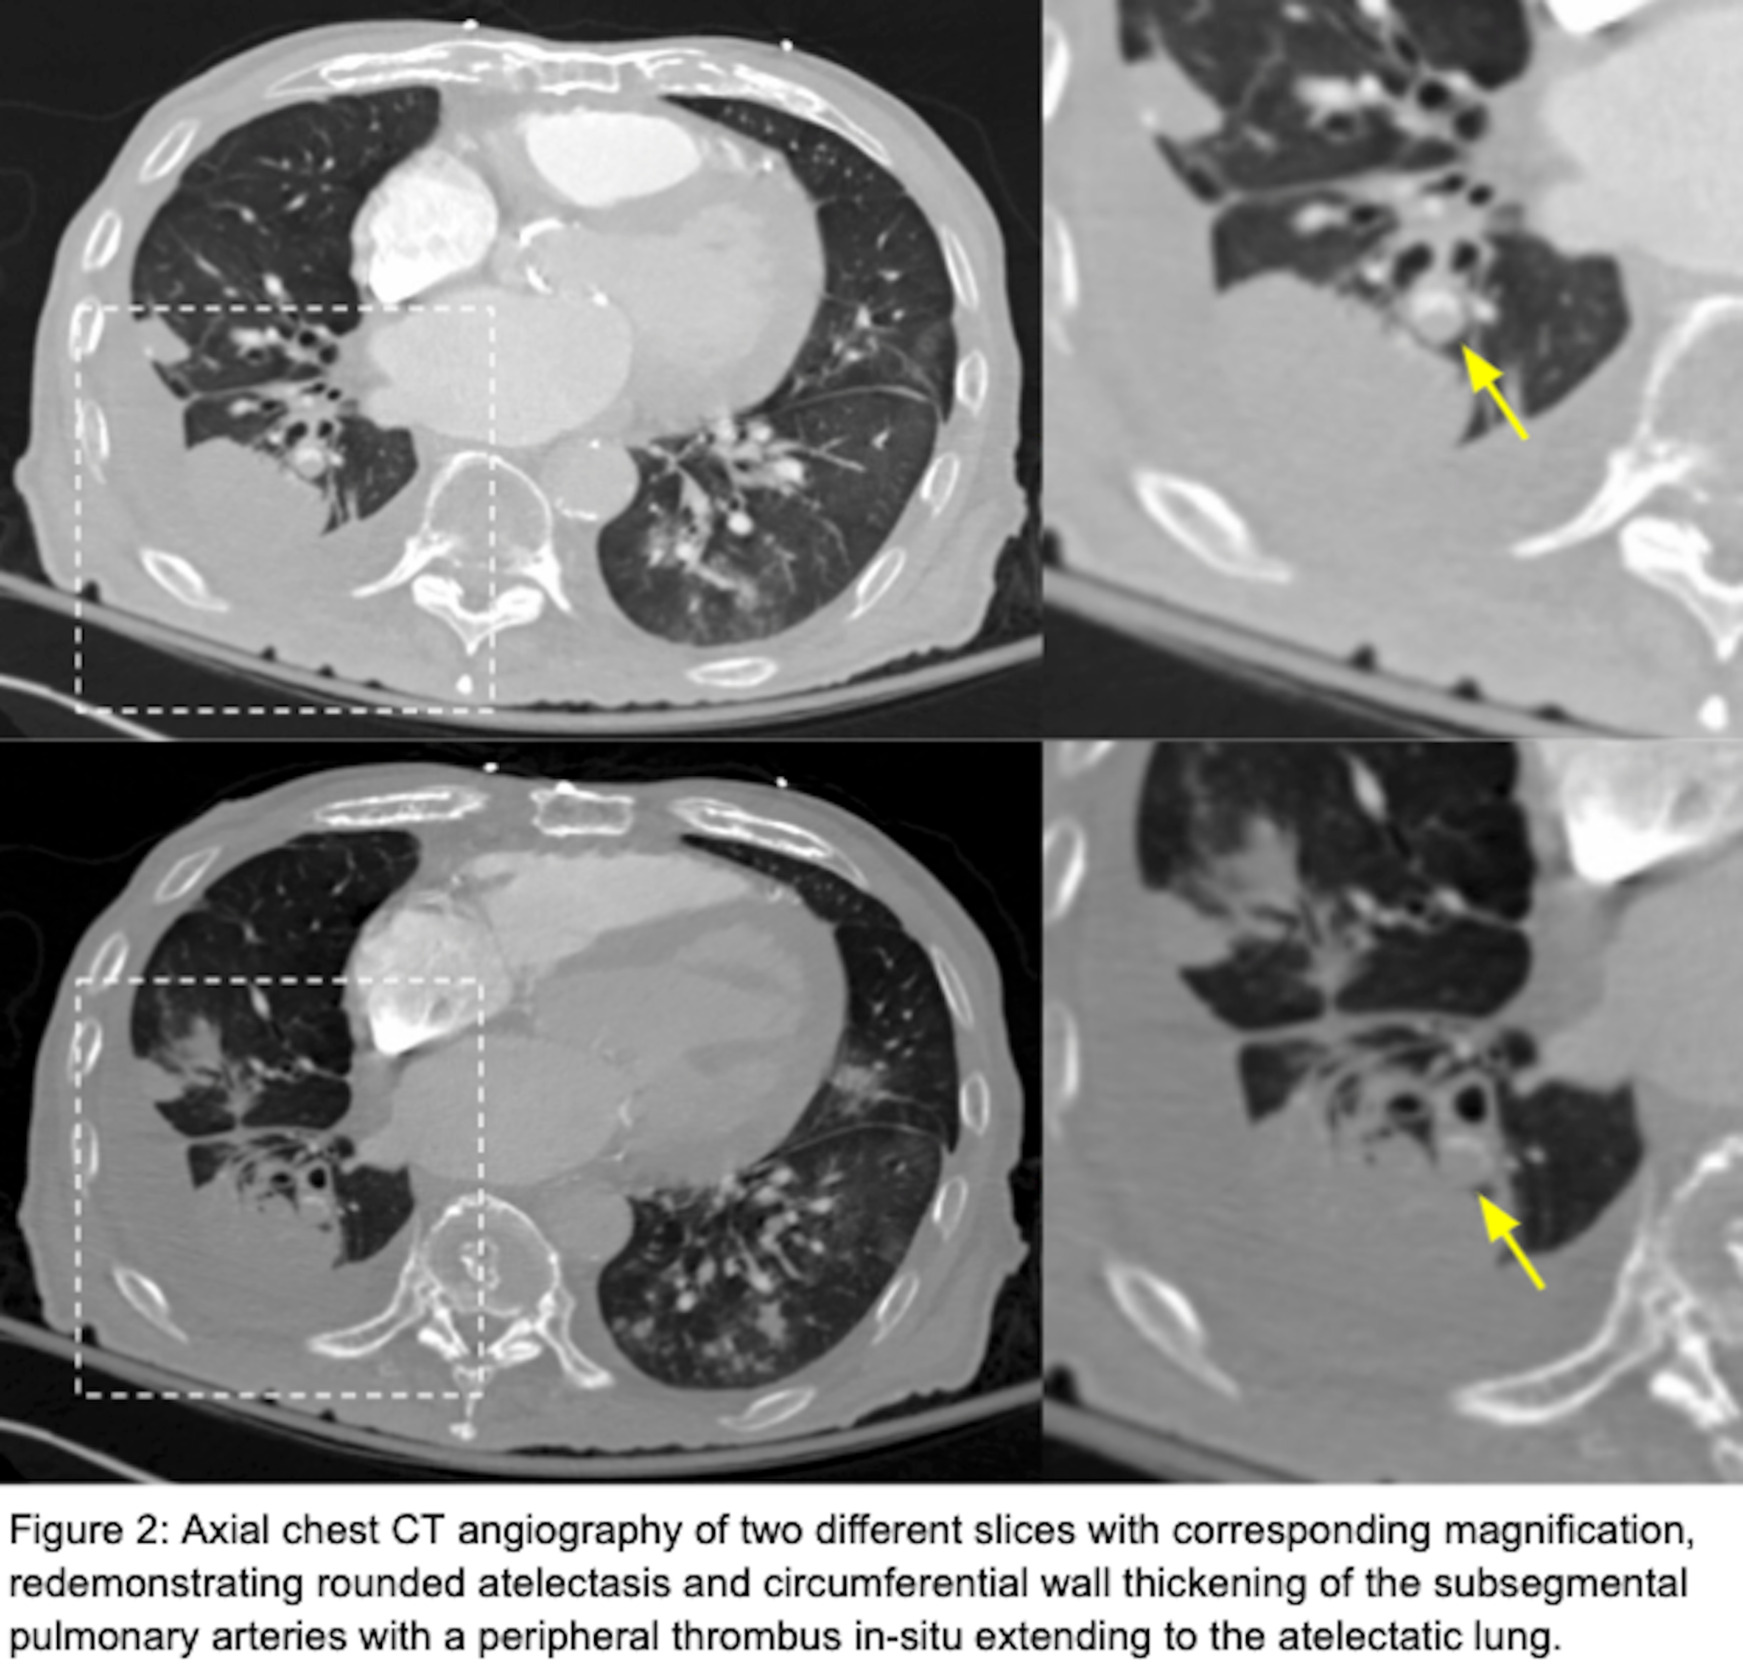

He had a chest radiograph on admission demonstrating patchy bibasilar opacities, with small bilateral pleural effusions which were greater on the right. Chest computed tomography angiography (CTA ) demonstrated a small chronic loculated right-sided pleural effusion with pleural thickening and pleural calcifications. Adjacent to this pleural effusion, there was a round opacity with evidence of volume loss and a comet tail sign compatible with rounded atelectasis. There was also demonstration of circumferential wall thickening of right basilar segmental and subsegmental pulmonary arteries with a peripheral thrombus within both of these pulmonary arteries extending to the rounded atelectasis (Figures 1 and 2). This was favored to represent an in-situ thrombus over a pulmonary embolism. Additional findings were concerning multifocal pneumonia versus aspiration, a second area of rounded atelectasis in the right middle lobe, subpleural reticular opacities, cardiomegaly, mediastinal and hilar adenopathy, and a small left pleural effusion. His CT imaging was then followed by a bilateral lower extremity venous duplex ultrasound, which was negative for evidence of deep venous thrombosis (DVT). A formal echocardiogram revealed a moderately dilated left ventricle with an ejection fraction of 15%, moderately dilated right ventricle with severely reduced systolic function, moderate-to-severe mitral regurgitation and normal pulmonary pressures. Imaging from one year prior to this admission demonstrated unchanged right lower lobe rounded atelectasis with no radiographic evidence of a thrombus in this area, although this is of limited interpretation due to the type of study performed. A previous echocardiogram from one-year prior revealed mitral regurgitation, and a globally hypokinetic left ventricle with an ejection fraction of 20-25%.

This case report identifies a patient with right-sided rounded atelectasis with in-situ thrombus in the supplying segmental and subsegmental arteries, a rare radiological finding. Both the rounded atelectasis and in-situ thrombus likely did not contribute to this patient’s acute respiratory decline, as the rounded atelectasis was demonstrated to be unchanged over a one-year interval; further, the thrombus was located in the periphery in segmental/subsegmental arteries supplying the rounded atelectasis, an area which was contributing to anatomical dead space. Additionally, image-based signs suggestive of an acute pulmonary embolism were not observed. These include pulmonary artery dilation proximal to the thrombus and a central filling defect with acute angles within vessel walls.3 Moreover, signs suggestive of a significant pulmonary embolism causing tricuspid regurgitation, or retrograde contrast flow into the inferior vena cava were not observed. On the contrary, we did observe pulmonary artery wall thickening without proximal dilation and a filling defect with obtuse angles surrounding the thrombus, which suggests this was not an acute thrombus but rather chronic. Collectively, these findings represent chronic changes and are interesting radiological findings. The association between rounded atelectasis and in-situ thrombus has not been previously described in a recent review2 or found elsewhere in the literature.